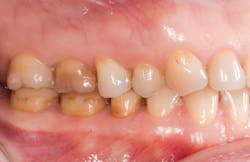

A patient presented with multiple deficient restorations, discolored teeth, and attrition (figures 1–4). The patient’s treatment plan was a full-mouth rehabilitation with a combination of veneers, crowns, and onlays.